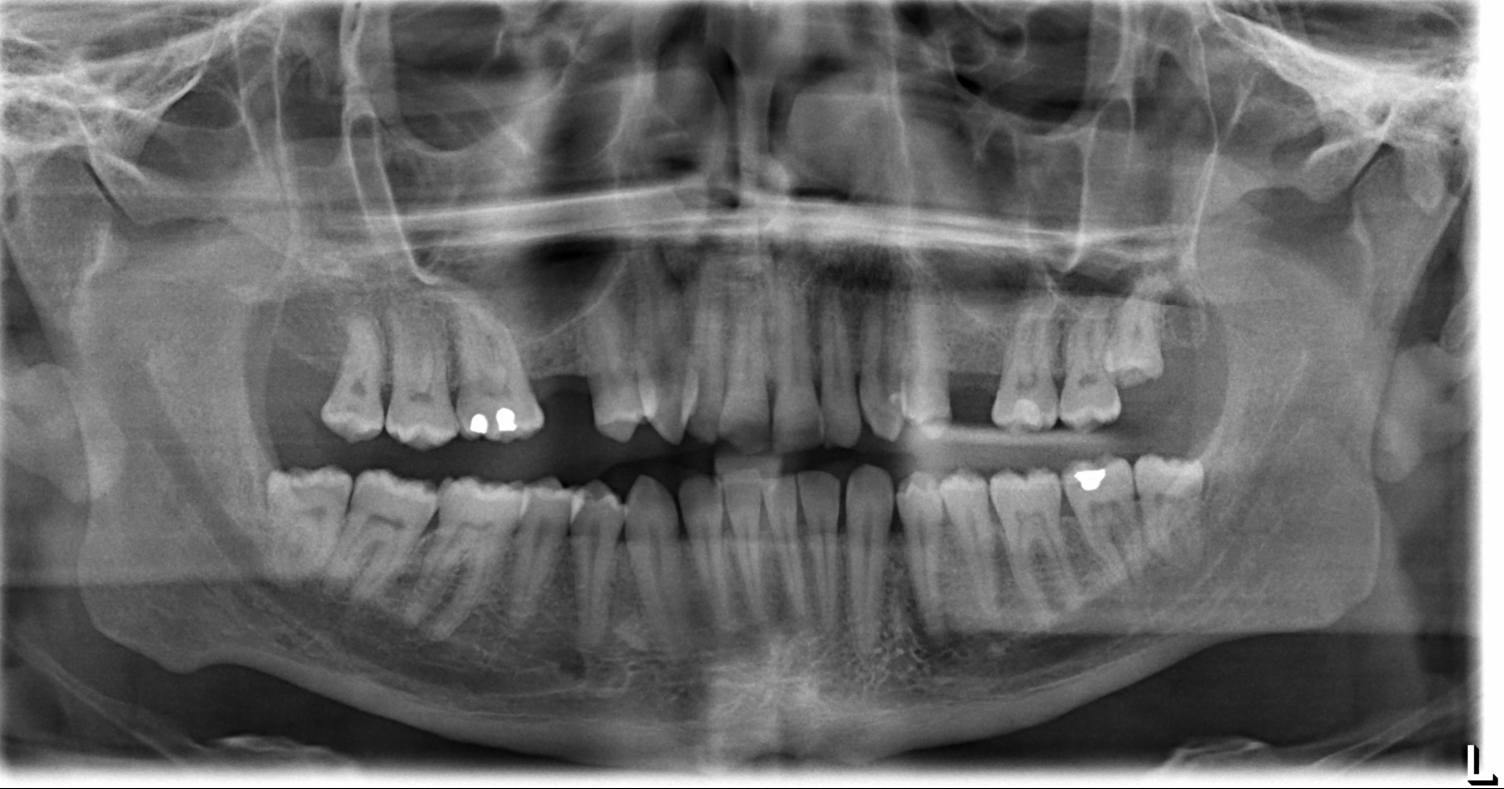

The most common symptom of bilateral coronoid hyperplasia is limitation of mandibular opening without visible facial deformity. The etiology and pathogenesis of coronoid hyperplasia are unclear. The condition can be diagnosed by panoramic radiographs and/or with 3-dimensional CT reconstructions.